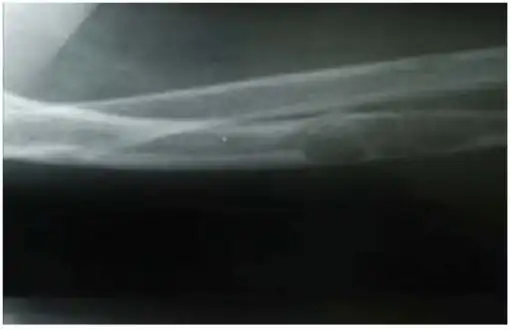

Lateral X-ray of the right radioulna showing osteitis fibrosa cystica lesion of ulna diaphysis with a pathologic fracture

X-rays may also be used to diagnose the disease. Usually, these X-rays will show extremely thin bones, which are often bowed or fractured. However, such symptoms are also associated with other bone diseases, such as osteopenia or osteoporosis.[29] Generally, the first bones to show symptoms via X-ray are the fingers.[22] Furthermore, brown tumors, especially when manifested on facial bones, can be misdiagnosed as cancerous.[29] Radiographs distinctly show bone resorption and X-rays of the skull may depict an image often described as "ground glass" or "salt and pepper".[30][31] Dental X-rays may also be abnormal.[2]